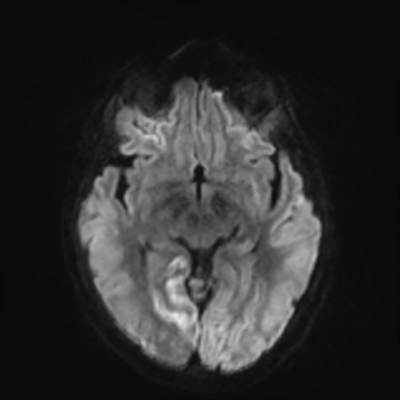

MRI brain (DWI)

You can clearly see diffuse cortical and basal ganglia diffusion restriction, and that of his deep cerebellar nuclei as well. The right occipital lobe abnormalities are a little more prominent, but then you remember that he is known to have had a right occipital stroke weeks ago.

In reviewing his data, you know that he doesn't have any of the strong predictors of a poor neurologic prognosis. However, based on these findings on MRI, along with the absent reactivity on cEEG, you are able to tell the primary team and the patient's family that he is likely to have a poor prognosis, based on these multiple moderate predictors. Recovery is not completely impossible-- there is more uncertainty with this prognostication than if we were able to get SSEPs-- but you're very worried about his outlook and that any potential recovery would require a very protracted rehabilitation period. Given his high cervical cord injury level, tracheostomy would be required anyway. So, it comes down to whether his family thinks he'd want to pursue these aggressive measures.